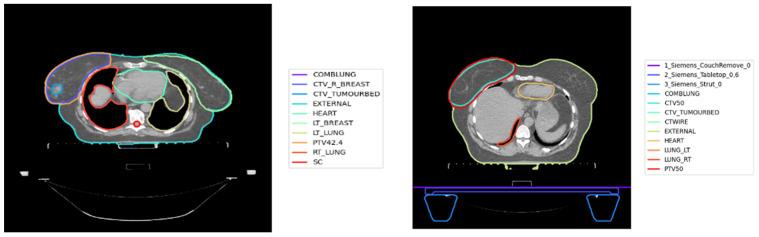

In progressing the use of big data in health systems, standardised nomenclature is required to enable data pooling and analyses. In many radiotherapy planning systems and their data archives, target volumes (TV) and organ-at-risk (OAR) structure nomenclature has not been standardised. Machine learning (ML) has been utilised to standardise volumes nomenclature in retrospective datasets. However, only subsets of the structures have been targeted. Within this paper, we proposed a new approach for standardising all the structures nomenclature by using multi-modal artificial neural networks. A cohort consisting of 1613 breast cancer patients treated with radiotherapy was identified from Liverpool & Macarthur Cancer Therapy Centres, NSW, Australia. Four types of volume characteristics were generated to represent each target and OAR volume: textual features, geometric features, dosimetry features, and imaging data. Five datasets were created from the original cohort, the first four represented different subsets of volumes and the last one represented the whole list of volumes. For each dataset, 15 sets of combinations of features were generated to investigate the effect of using different characteristics on the standardisation performance. The best model reported 99.416% classification accuracy over the hold-out sample when used to standardise all the nomenclatures in a breast cancer radiotherapy plan into 21 classes. Our results showed that ML based automation methods can be used for standardising naming conventions in a radiotherapy plan taking into consideration the inclusion of multiple modalities to better represent each volume.